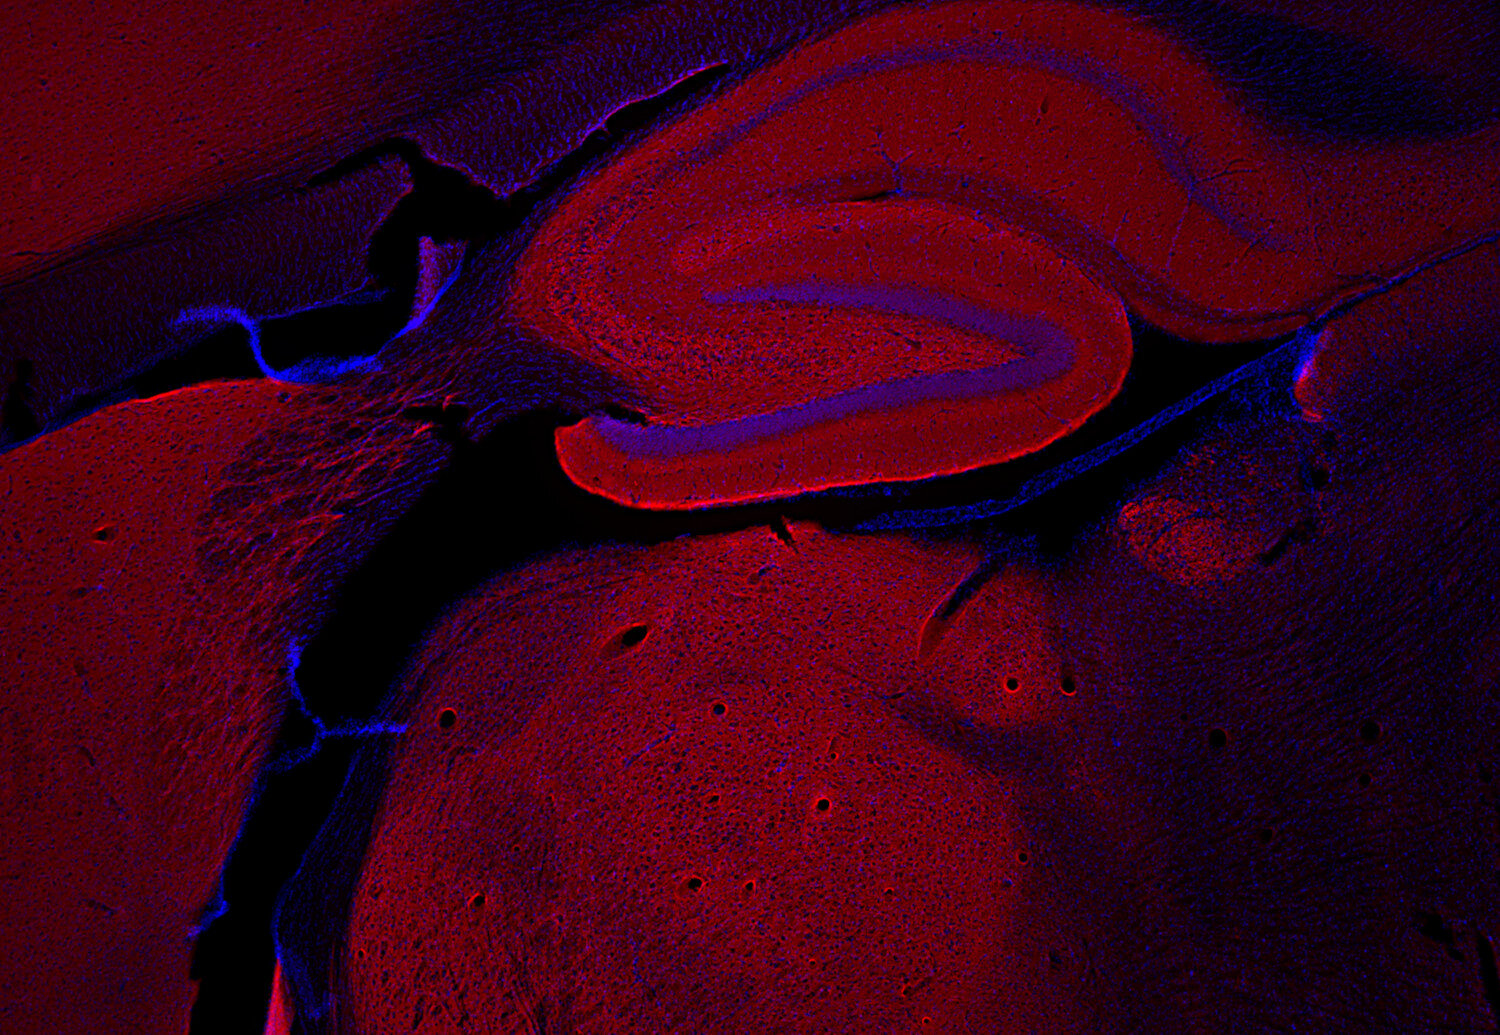

IHC: 1 : 500 gallery

Immunohistochemistry (IHC) on 4% PFA perfusion fixed tissue with 24h PFA post fixation. Immunoreactivity is usually revealed by fluorescence or a chromogenic substrate. Some antibodies require special fixation methods or antigen retrieval steps. For details, please refer to the ”Remarks” section.